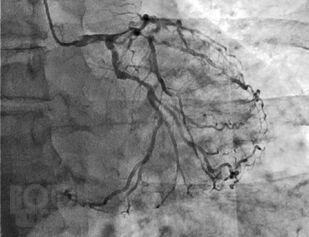

Учебно-методическое пособие содержит данные об этиологии сахарного диабета и сердечно-сосудистых заболеваний, о механизмах развития атеросклероза при сахарном диабете. Продемонстрирована взаимосвязь сахарного диабета и сердечно-сосудистых заболеваний, вызванных атеросклерозом. Представлена информация о необходимости не только достижения целевого содержания глюкозы и гликированного гемоглобина, но в первую очередь влияния на риски развития сердечно-сосудистых осложнений. Подробно рассмотрена терапия как глюкозоснижающими, так и кардиологическими препаратами.